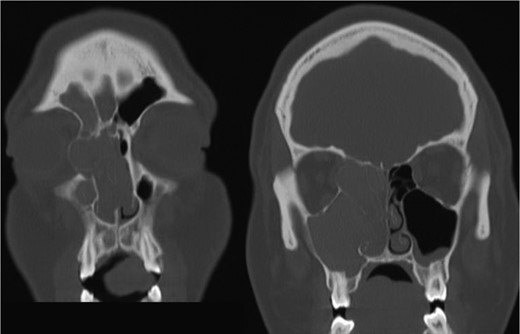

Axial CT view of the ethmoid labyrinth with the left side super imposed on the right side over the midline for comparison.

AFS is a known risk factor for development of nasal polyps [5, 6]. Incidences of AFS causing unilateral proptosis have also been described in the literature [7, 8]. The findings from the current CT, however, indicate a unique developmental process. When compared to the patient’s left side, the extent is easily seen (Fig. 3). In consideration of the preservation of the ethmoid architecture along with the patient’s age, it appears that due to the severity and duration of the polyposis and AFS, the ethmoidal labyrinth malformed while still in development. Contrastingly, in cases of several nasal polyposis, including those with ocular involvement, bone erosion and destruction are most frequently seen with respect to changes in bone anatomy [9]. Chronic remodeling of the ethmoid bone has been described in venous malformations [10], however, cases of nasal polyps leading to bone malformation are significantly underrepresented in the literature. CT imaging proved the most valuable diagnostic tool in examining the extent of the proptosis secondary to polyposis, as well as describing the changes in the ethmoid labyrinth structure. Surgical approach proved effective in reducing the patient’s symptoms, as well as confirming the etiology of the unilateral proptosis.